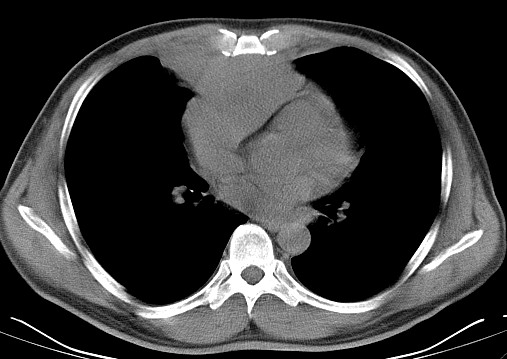

男   40   反复腹痛入院行彩超检查示胸骨右缘4、5肋间不均质回声团

淋巴瘤:前纵隔可见多组肿大的淋巴结,部分融合,有液化坏死

上区却那么有点象占位,胸腺瘤不太象,一点强化也没有,淋巴瘤气管前上腔静后却很干净,下区也点象纵隔积血征,